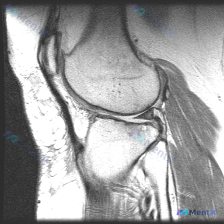

看到一个很有代表性的读片病例,整理了一下病例和分析思路分享给大家。 病例基本信息 这是一张膝关节MRI矢状位T1加权像,临床提示怀疑存在软骨异常,需要我们读片分析。 影像读片结果 先给大家说下完整的读片发现: 1. 序列与定位确认:这是标准的膝关节矢状位T1加权像,左侧为前,右侧为后,上方是股骨远端...

整理了一份很有参考意义的影像读片病例,核心问题是:这张膝关节MRI-T1序列矢状位图像上,能观察到软骨异常吗?把整个分析思路分享给大家。 一、影像基础信息 这是一幅标准的膝关节矢状位T1加权像,图像对比度良好,骨髓腔呈正常高信号(脂肪髓),皮质骨呈低信号,解剖结构显示清晰,无明显运动或金属伪影;图像...

遇到一个挺典型的读片问题,整理出来和大家分享一下思路: 病例背景 临床关注点:怀疑膝关节软骨异常,提供单张膝关节MRI矢状位T1加权像(T1WI)读片 影像基础评估结果 先把影像上能看到的情况理清楚: 1. 骨性结构:股骨远端、胫骨近端皮质连续,没有骨折;骨髓信号是正常脂肪骨髓的灰白色信号,没有局灶...

今天遇到一个有意思的读片问题:临床怀疑膝关节软骨异常,但提供的单张矢状位T1加权MRI读下来基本正常,整理一下分析思路和大家分享。 一、现有病例影像资料整理 这是一张膝关节矢状位T1加权MRI,图像质量清晰,信噪比良好,可见层面包含股骨远端外侧髁、胫骨近端、后交叉韧带、半月板前后角、髌韧带及Hoff...